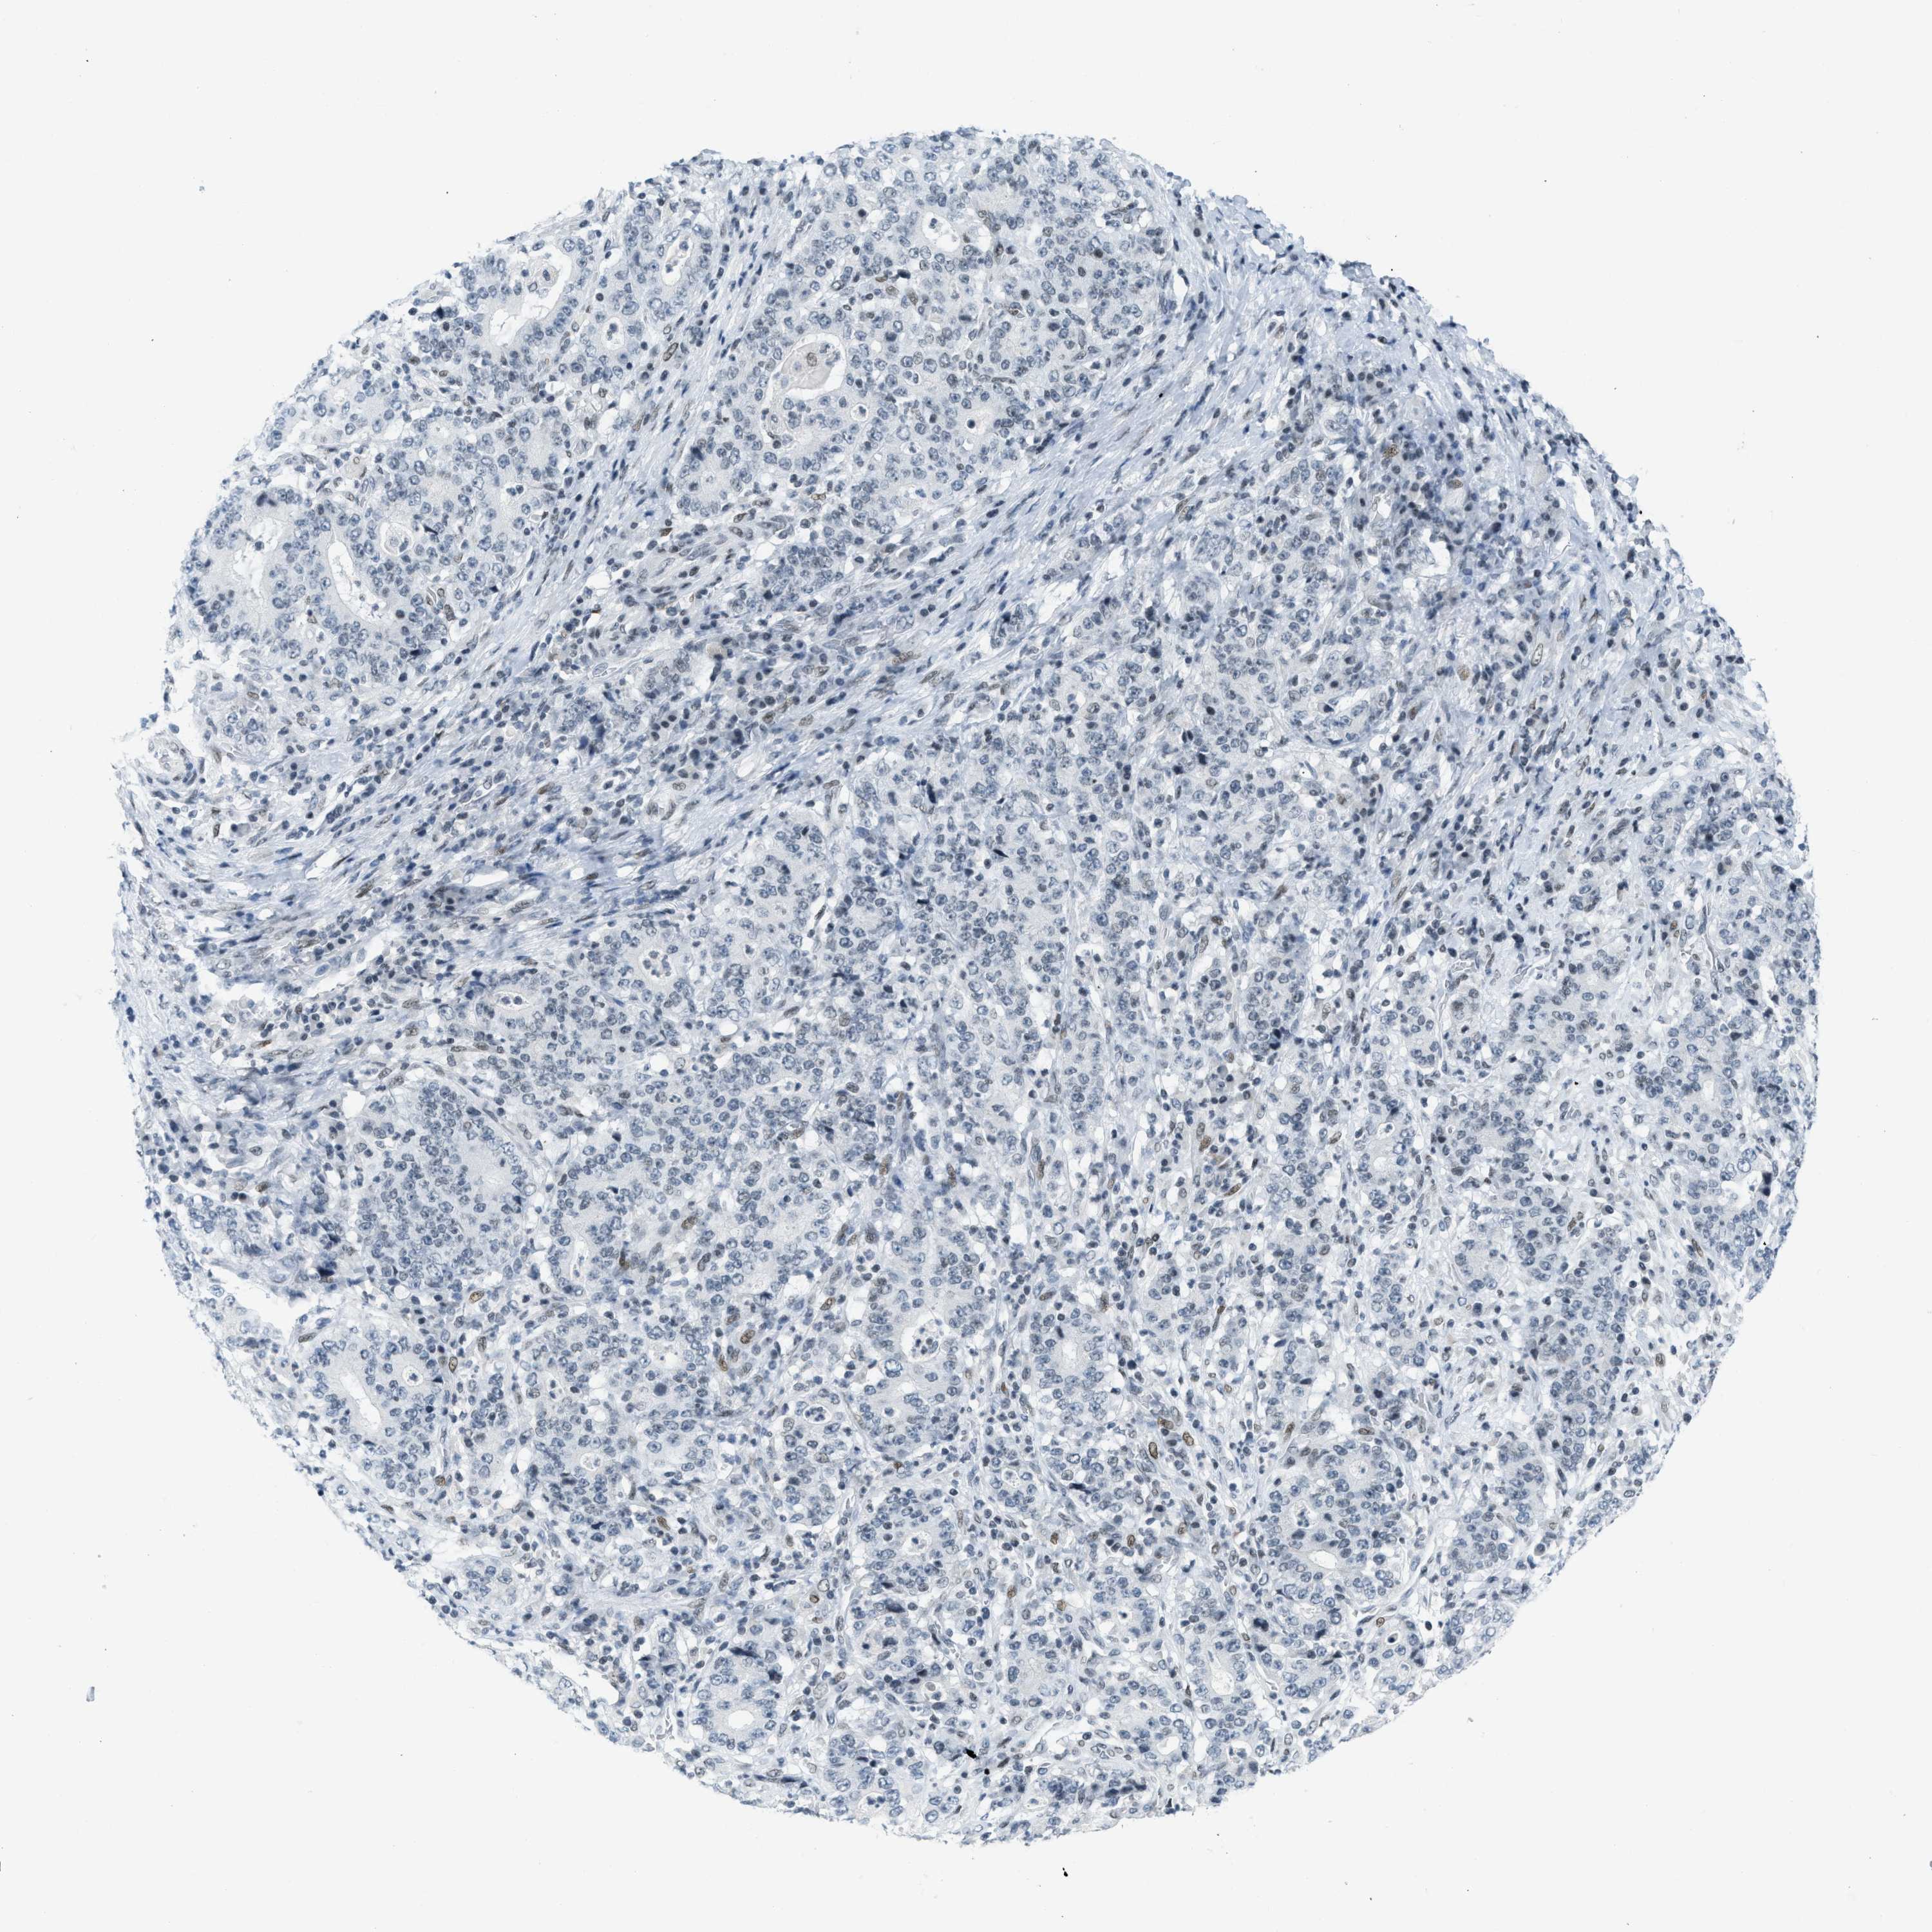

STOMACH CANCER - Protein expressioni

A mouse-over function shows sample information and annotation data. Click on an image to view it in a full screen mode. Samples can be filtered based on level of antibody staining by selecting one or several of the following categories: high, medium, low and not detected. The assay and annotation is described here.

Note that samples used for immunohistochemistry by the Human Protein Atlas do not correspond to samples in the TCGA dataset.

Antibody stainingi

Antibody staining in the annotated cell types in the current human tissue is reported as not detected, low, medium, or high, based on conventional immunohistochemistry profiling in selected tissues. This score is based on the combination of the staining intensity and fraction of stained cells.

Each image is clickable and will lead to virtual microscopy that enables deeper exploration of all samples and also displays staining intensity scores, fraction scores and subcellular localization as well as patient and tissue information for each sample.

Antibody CAB018768

Staining

High

Medium

Low

Not detected

Intensity

Strong

Moderate

Weak

Negative

Quantity

>75%

75%-25%

<25%

None

Location

Nuclear

Cytoplasmic/membranous

Cytoplasmic/membranous,nuclear

Adenocarcinoma, NOS